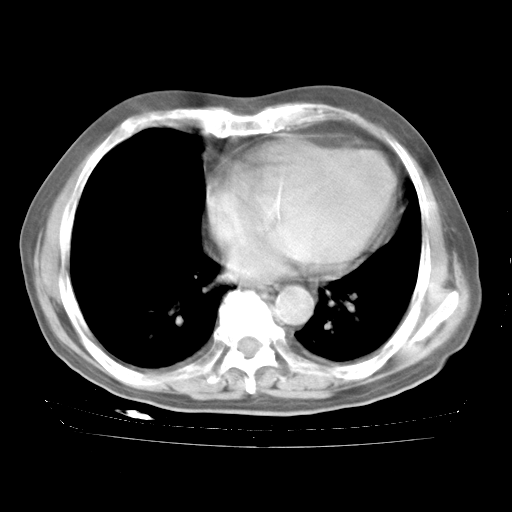

4月28日肺部CT——再次出现类似去年5月9日——透光度降低,“间质性”改变。

4月28日肺部CT——再次出现类似去年5月9日——磨玻璃样、间有“粟粒样”改变。